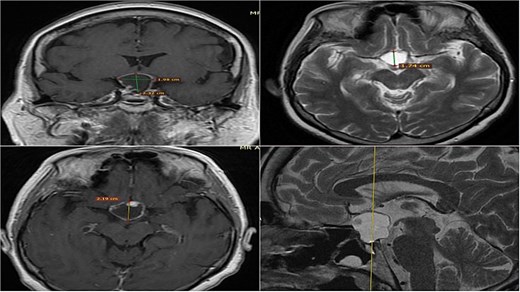

A 71-year-old woman who gradually began with bitemporal hemianopia, progressing to amaurosis of the right eye, adding diabetes insipidus. An MRI study obtained the following images (Fig. 1). 3D reconstruction was performed by manual segmentation to obtain the anatomy of the tumor and its vascular relationships. For this segmentation, it was necessary to splice T2, T1, Contrast, and 3D TOF sequences (Fig. 2). The importance of the reconstruction lies in being able to adequately observe most of the cerebral blood circle and its relationships with the tumor. At the time of carrying out the transnasal resection surgery and keeping in mind the proximity of the anterior communicating artery with the dorso-ventral region of the tumor, the capsule was resected with excessive caution to avoid generating excessive traction and thus avoiding injuries—important vascular (Fig. 3).

MRI of sellar region tumor in contrasted T2 and T1 sequences in axial, coronal and sagittal sections.